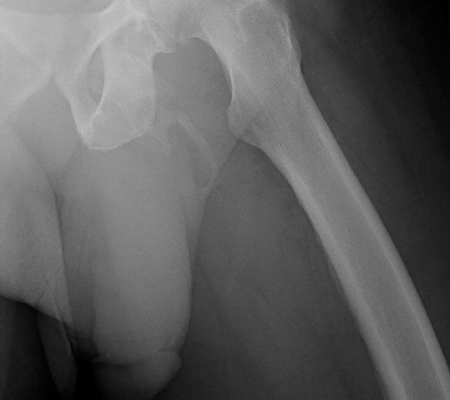

(Foto: Urology Case Reports)

Os autores escreveram que as imagens mostravam uma “calcificação extensa em forma de placa ao longo da distribuição esperada do pênis”. O paciente havia se queixado aos médicos de dor peniana, mas não teve nenhum outro sintoma, o que retardou o diagnóstico da rara doença de Peyronie.